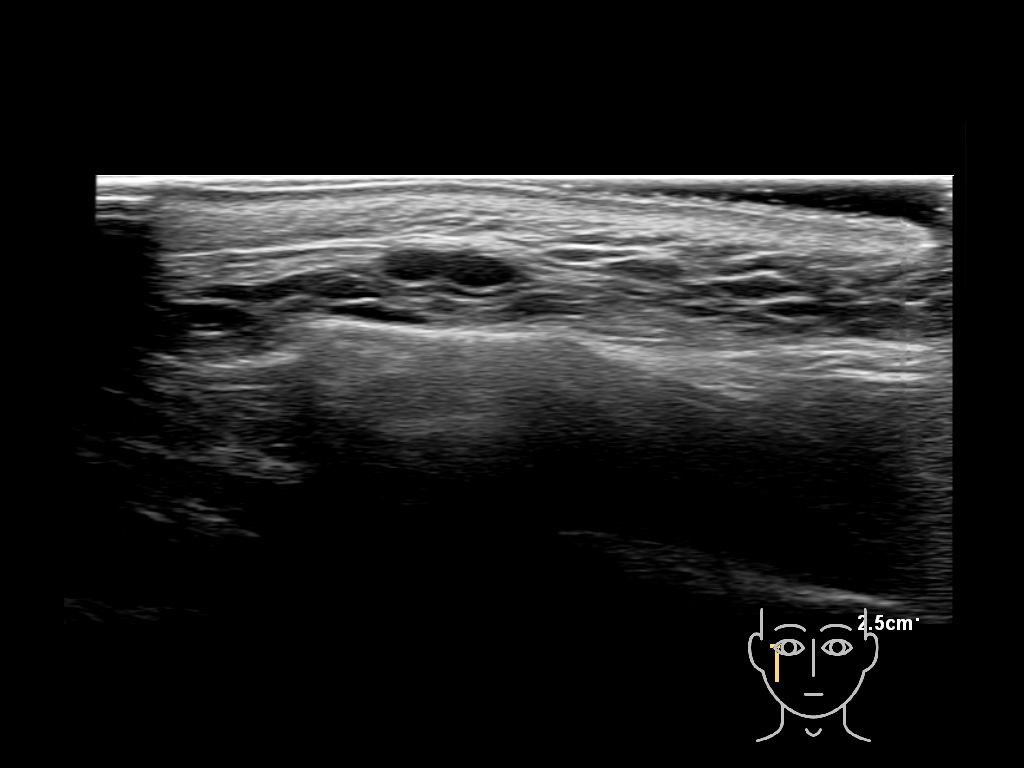

Filler deposits may end up unintentionally in the SMAS or fascial layers of the skin. Very often this will not lead to adverse events, however, adverse events ( nodules, migration / redistribution impaired muscle movement and smiling and malar edema) are are often related to filler ending up in the SMAS or fascia.

Study the first image to recognize the different layers. If you are sure about the layers, swipe to the second image to view the answer (if applicable).